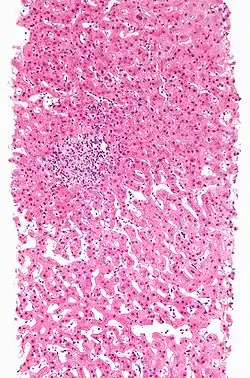

| A rash due to a drug reaction |